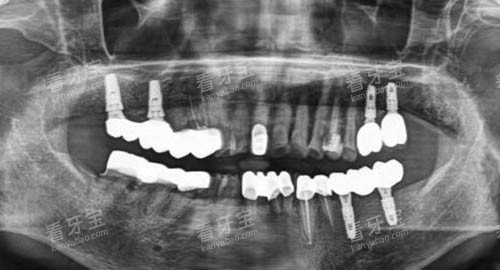

为了给患者提供更加比较准、较高的效率的口腔医疗服务,大连齿医生口腔引进了一系列国内外靠前的口腔医疗设备。

这些设备包括智能化口腔全景机、口腔 CT、激光治疗仪等。

智能化口腔全景机能够快速、更准地拍摄口腔全景图像,为医生提供超全的口腔信息,有助于医生做出更加更准的诊断;口腔 CT 则可以提供三维立体的口腔影像,让医生更加清晰地了解患者口腔内部的结构和病变情况;激光治疗仪在治疗口腔疾病时,具有创伤小、疼痛轻、修养快等优点,能够为患者减轻痛苦。

在种植牙方面,大连齿医生口腔的种植成功几率非常高,患者在种植牙齿后,能够修养正常的咀嚼功能,提高生活质量。